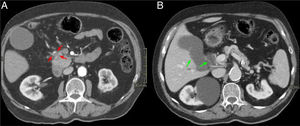

Mujer de 65 años con diarrea crónica. Cortes axiales del abdomen tras administración de CIV en fase portal (A y B). Tenue hipodensidad en la cabeza-proceso uncinado del páncreas que contacta con la vena mesentérica superior (flechas rojas, A). Dilatación de la vía biliar extrahepática y del CP (signo del doble conducto) (flechas verdes, B) y borramiento del surco pancreaticoduodenal (asterisco rojo, A). Hallazgos sugestivos de neoplasia de páncreas.

Mismo paciente de la Figura 9. Cortes axiales del abdomen en secuencia T1 FS poscontraste (VIBE). A y B) Masa hipointensa en cabeza pancreática respecto al resto del páncreas con ocupación del surco pancreaticoduodenal (flecha y asterisco rojos, A) y dilatación de vía biliar extrahepática y del CP (flechas verdes, B). El diagnóstico final fue de adenocarcinoma de páncreas.

El engrosamiento de la pared del duodeno con estenosis luminal secundaria y quistes en su pared o en el surco son hallazgos infrecuentes en el ACP, cuya presencia haría inclinarse hacia el diagnóstico de PS. Sin embargo, la existencia de una masa hipointensa en T1 con invasión vascular, adenopatías o infiltración del retroperitoneo haría más factible el diagnóstico de ACP (figs. 7 y 8)7,9,10. Otro hallazgo que diferencia el ACP de la PS es una dilatación, tanto del CPP como del colédoco (signo del doble conducto) (figs. 9 y 10)8. El patrón de realce de estas dos entidades en estudios poscontraste es también diferente y ayuda a diferenciar ambas entidades. El ACP presenta escaso realce y de forma homogénea, mientras que la PS suele realzar de forma tardía y heterogénea7.

Existen otros hallazgos radiológicos descritos que no ayudan a diferenciar la PS del ACP, como, por ejemplo, la dilatación del CPP o del colédoco, ya que, por localización anatómica, ambos se pueden ver afectados en las dos entidades2,3, aunque en casos de PS la estenosis del colédoco suele ser regular y lisa y en casos de ACP suele ser irregular y abrupta2.